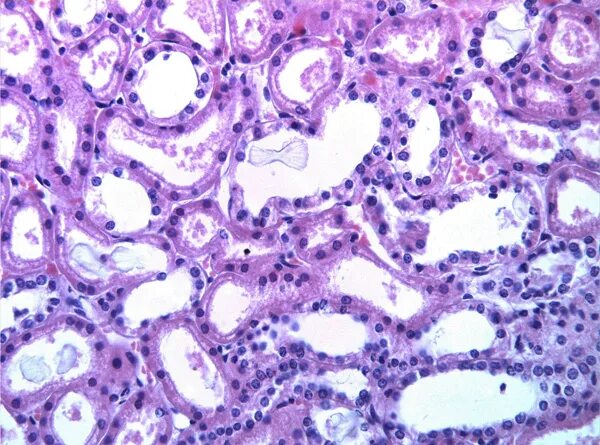

Срочные гистологические исследования